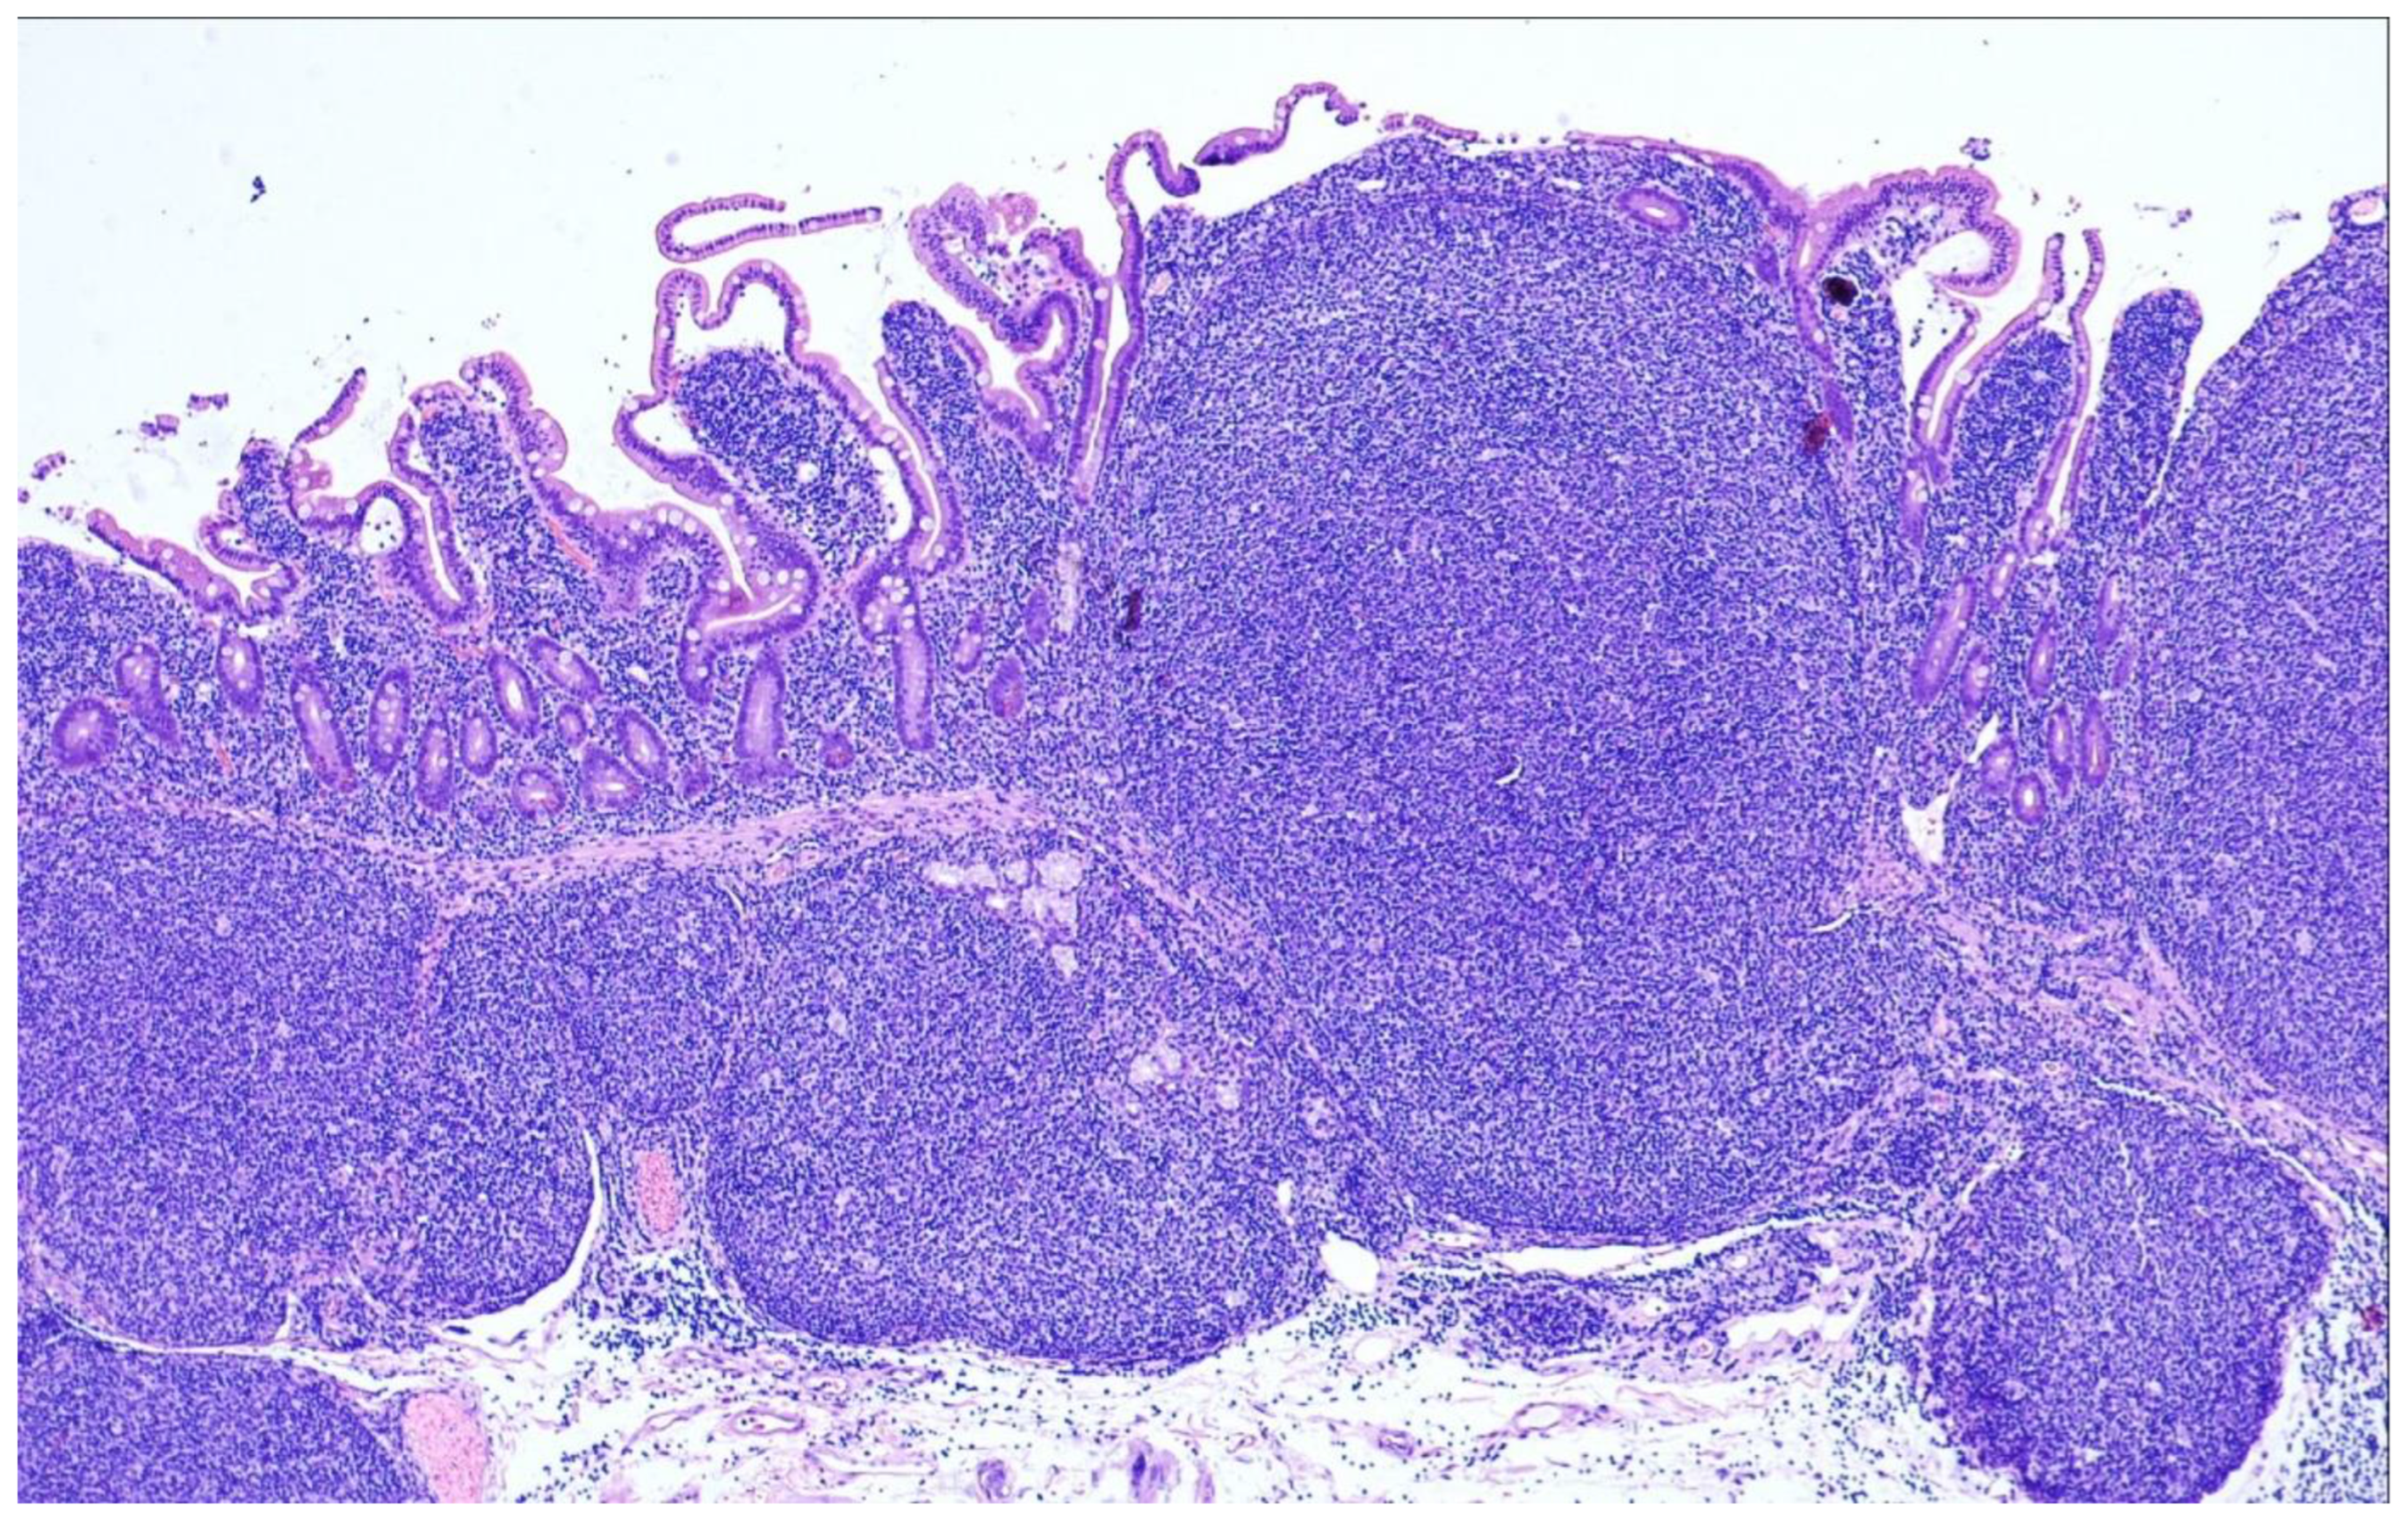

9. Duodenal-Type Follicular Lymphoma

- Tsuyama, N.; Yokoyama, M.; Fujisaki, J.; Oguchi, M.; Terui, Y.; Takeuchi, K. Villous colonization (glove balloon sign): A histopathological diagnostic marker for follicular lymphomas with duodenal involvement including duodenal-type follicular lymphoma. Pathol. Int. 2019, 69, 48–50. [Google Scholar] [CrossRef] [PubMed]